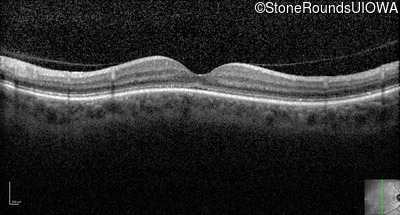

Optical Coherence Tomography - Right - 20/200 sc

Exemplar / OCT Stack

OCT Stack